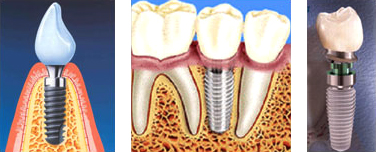

임플란트는 순수 타이타늄으로 만든 인공치아를 잇몸뼈에 심은 후 치아를 수복하는 현대 치의학의 혁신적인 치료방법입니다.

임플란트의 구조

임플란트의 재료는 순수 타이타늄을 사용하는데 생체적합성, 생체 역학적 기능성, 그리고 생물학적 안정성을 갖는 재료로서 오랜기간 동안의 실험을 통하여 인체에 안전한 재료로, 인공치아 임플란트 뿐 만아니라 구강악안면외과 영역, 정형외과 영역, 신경외과 영역 등 대부분의 의학분야에서도 뼈나 치아를 대체하는 물질로서 광범위하게 사용되고 있습니다.

- 보철물의 완성

만들어진 기둥 주위의 잇몸이 보기좋게 아물게 되면 치아모형을 만들어 최종의 보철물을 연결하게 됩니다.